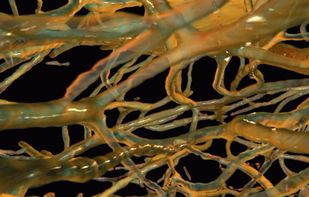

OsiriX is an image processing software dedicated to DICOM images (".dcm" / ".DCM" extension) produced by imaging equipment (MRI, CT, PET, PET-CT, SPECT-CT, Ultrasounds, ...). It is fully compliant with the DICOM standard for image comunication and image file...

AMIDE is a completely free tool for viewing, analyzing, and registering volumetric medical imaging data sets such as SPECT/PET/CT. Renderization in 3D and much more...

Drishti is an open-source scientific visualisation software been developed with its end use in mind: ie. visualising volumetric data, such as tomography data, electron-microscopy data, etc.